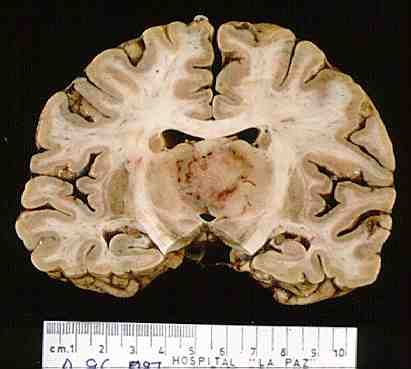

33.- Aspecto macroscópico de Linfoma afectando a ambos tálamos por la línea media.